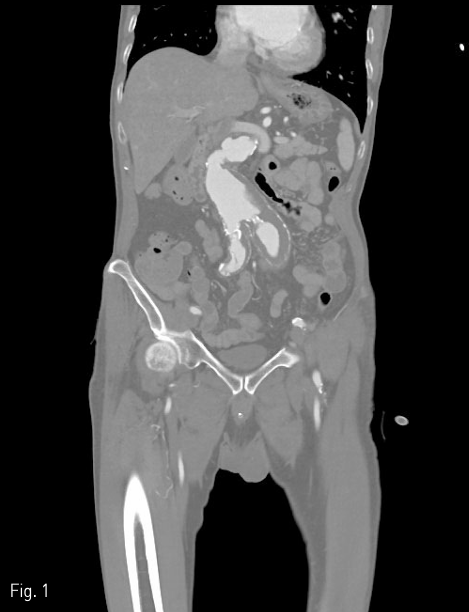

2018년 좌측발의 통증과 색깔변화를 주소로 내원하여 시행한 조영증강 CT(Fig. 1)상에서 발견된 복부대동맥 및 양측 장골 동맥류에 대해 InCraft(Cordis, Milpats, US)를 이용한 EVAR 치료(Fig. 2)를 받은 환자로, 술후 퇴원전 조영증강 CT(Fig. 3)상에서 우측 장골 분지 인조혈관이 폐색된 소견을 보였다.

시술 1개월 뒤 시행한 조영증상 CT에서 양측 장골 분지 인조혈관 내강은 잘 유지되었다(Fig. 6A&B).

Fig 6B

(A,B) CT angiography obtained 1 month later the procedure shows patent intraluminal space of bilateral iliac limb graft.